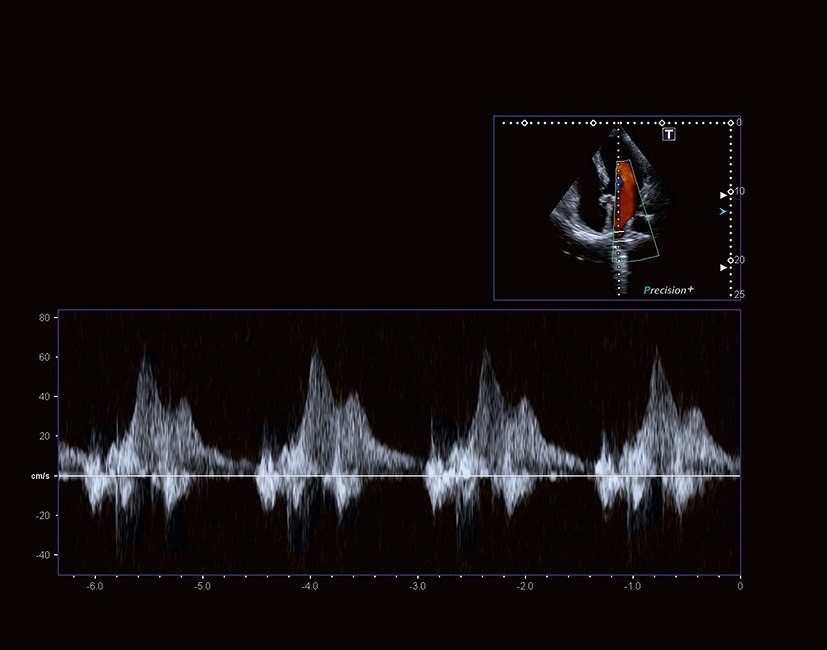

تکنولوژی پردازش سیگنال و پروب های با پهنای باند وسیع Aplio حساسیت، نفوذ و قدرت تفکیک مکانی فوق العاده را برای تمام حالات داپلر به ارمغان می آورد.

Aplio تصاویر Tissue Doppler و طیف های Pulsed Wave TDI با frame rate بالایی را به منظور زمان بندی دقیق فعالیت قلبی، به دو صورت بصری و کمّی، برای شما مهیا می‌کند.